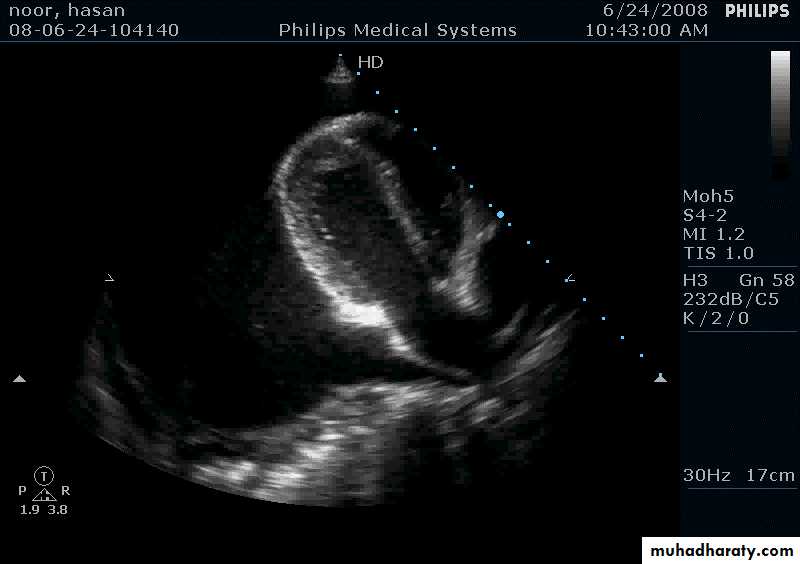

Echocardiography

Thickening of pericardiumPericardial effusion

Pericardial Effusion: Investigation

Echocardiography: establishes the diagnosis31